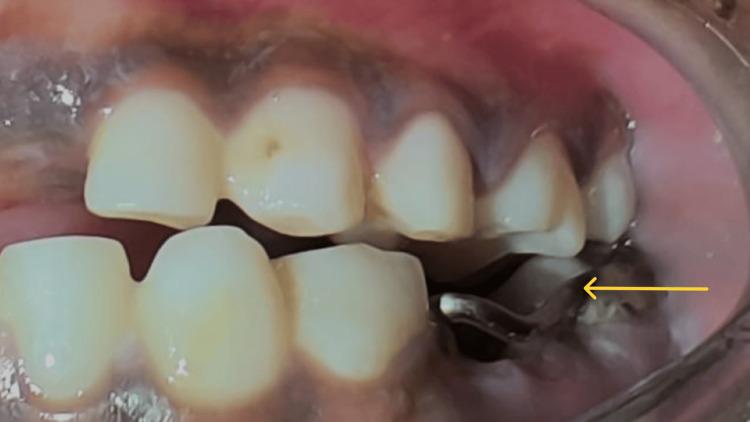

Oral health is a vital part of overall health, particularly for children with special healthcare requirements. The terms "dumb" and "mute" are frequently linked with the term "deaf" due to the connection between hearing loss and speech impairment. A hearing and speech-impaired child may be unable to express completely because of the communication barriers. It is important to treat special children with utmost care and safety. This case report describes the dental management of an 8-year-old special child reported with multiple carious lesions under general anesthesia as she was not well acquainted with sign language. In a hospital setting under general anesthesia (GA), all necessary treatments are carried out in a single appointment. Since it is monitored by a multi-disciplinary team it can safely provide effective care to a child with hearing impairment and mutism.

口腔健康是整体健康的重要组成部分,对于有特殊医疗需求的儿童尤为如此。由于听力丧失与言语障碍之间的关联,“哑巴”和“缄默”这两个词经常与“聋”这个词联系在一起。有听力和言语障碍的儿童可能由于沟通障碍而无法完全表达自己。以最大程度的关怀和安全对待特殊儿童非常重要。本病例报告描述了一名8岁特殊儿童的牙科治疗情况,该儿童因不太熟悉手语而在全身麻醉下被报告有多处龋损。在医院的全身麻醉(GA)环境下,所有必要的治疗都在一次就诊中完成。由于有一个多学科团队进行监测,它可以安全地为有听力障碍和缄默症的儿童提供有效的护理。